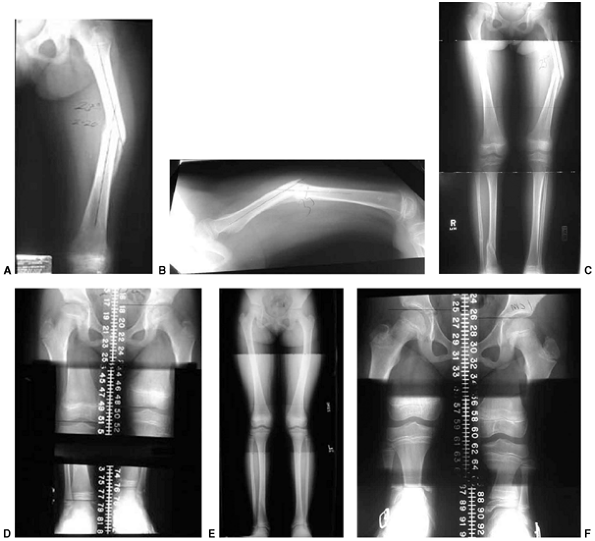

![]() |

|

Figure 33.1 Periosteal bone formation. A:

Complete fracture of the humeral diaphysis in a 6-month-old child. The periosteum is presumed to be intact on the compression (concave) side. B: Four weeks later, the periosteum has formed a complete column of new bone. C: Six months after injury, there has been significant remodeling, with a 50% correction of the angular deformity. |